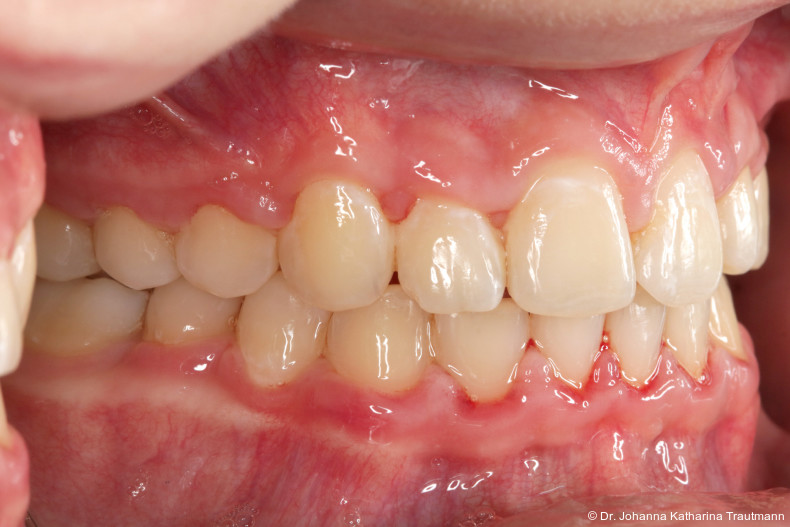

Im Rahmen der Multibrackettherapie wurde bewusst der Zahn 13 aus dem Hauptnivellie rungsbogen ausgelassen, um Kippungen und Asymmetrien im Zahnbogen zu vermeiden. Der Zahn 23 wurde locker mit einer Distanz ligatur angebunden, um eine weitere Bewegung nach vestibulär zu erreichen. Auf einem 0.019" x 0.025" Stahlbogen erfolgte anschlie ßend mittels Umgehungsbiegung sowie eines Overlaybogens (0.014" NiTi) die Integration des Zahnes 13 in den Zahnbogen. Die Zwischendiagnostik nach einem Jahr festsitzender Behandlung zeigte eine gelungene Bisshebung bei guter Nivellierung des Okklusionsplanums und orthoaxialer Einstellung der Frontzähne. Die Zahnbögen präsentierten sich harmonisch ausgeformt, es zeigte sich jedoch eine verbleibende Torqueproblematik an bei den Oberkiefereckzähnen. Nach Freilegung und Einstellung verlagerter Eckzähne ist eine korrekte Torque und Angulationssteuerung häufig eine Herausforderung. Während vestibulär verlagerte Zähne zu gingivalen Rezessionen neigen, behalten palatinal verlagerte Zähne oft ihre palatinale Wurzelstellung bei.13, 14 Die genutzte MBTPrescription der Brackets bietet die Möglichkeit, zwischen +7°, 0° und –7° Torque zu wählen.15 In einem 0.022" System ist bei Verwendung eines 0.019" x 0.025" Bogens jedoch mit einem Torqueverlust von etwa 10° zu rechnen.16

Eine rein klassische „Hochnivellierung“ führt daher zu keiner aus reichenden Torqueübertragung. Alternativ kann ein individualisiert eingebogener Einzelzahntorque eingesetzt werden, um diesen Verlust auszugleichen. Zum Zeitpunkt der Zwischendiagnostik bestand weiterhin eine asymmetrische Bisslage sowie ein vergrößerter Overjet, die beide im weiteren Verlauf mithilfe intermaxillärer Gummizüge korrigiert wurden. Bereits in dieser Phase erfolgte eine Rück sprache mit der Abteilung für Präventive Zahnmedizin, Parodontologie und Kariologie, um eine optimale Ausgangssituation für den späteren odontoplastischen Umbau des Zahnes 22 zu schaffen. Eine präzise kieferorthopädische Einstellung kann die restaurative In vasivität deutlich reduzieren und die Gewebe symmetrie, einschließlich Papillen und Gin giva verlauf, positiv beeinflussen.17, 18 Optimalerweise werden Funktion und Ästhetik vor Entfernung der Multibracketapparatur interdisziplinär abgestimmt, um sowohl aus kieferorthopädischer als auch konservierender Sicht das bestmögliche Ergebnis zu erzielen. Auch das Terminmanagement sollte frühzeitig abgestimmt werden, um eine zügige Rehabilitation zu gewährleisten.